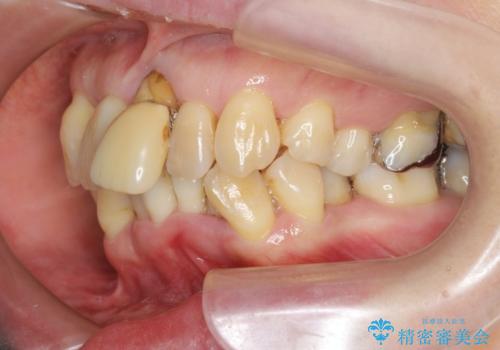

重度の歯周病で多数の歯を残せない問題、歯並び・噛み合わせの問題、欠損の問題、と多数の大きな問題が認められました。

このままの歯並びでは仮にインプラントを埋入したとしても歯ブラシがしづらく、また歯周病の問題が再発しやすい、と判断し矯正治療を行ったのちに歯周病治療、インプラント治療を行っていく治療計画としました。

インプラント治療に加え、歯周病に対しての再生治療や歯周ポケットの除去を行う歯周外科、矯正治療、と必要な治療は多岐に渡りましたが、最終的に安定した噛み合わせを得られたとともに、清掃のしやすい口腔内環境を確立できました。